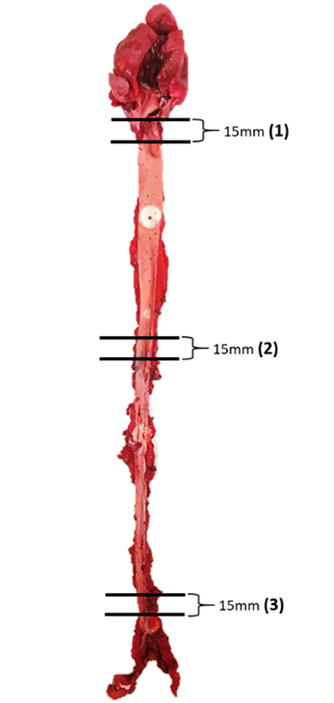

For histological evaluation, three different areas of aortic tissue were

sampled, i.e., 10 mm away from the aortic arch, 10 mm away from upper thoracic,

and 10 mm above the iliac bifurcation. Each section measured 15 mm in length

(Fig. 4). All the aortic specimens of the rabbits were fixed in 10% formalin

Fig. 4.Schematic diagram of the aortic tissue of rabbits and selected lesion sites for section analyses.

Three different sites of aortic tissue were sampled with each section measuring 15 mm in length. The number in parentheses indicates the representative areas of each part of the artery selected for tissue section and the measurement of intimal lesion areas. (1) At the origin of the aortic arch; (2) at the origin of the abdominal aorta; (3) at the end of abdominal aorta before the bifurcation of iliac artery.